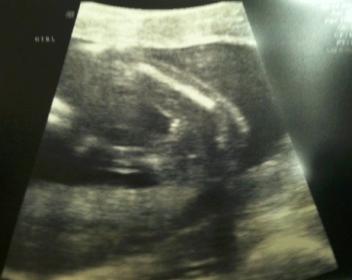

16 weeks - Tech says girl...

I figured I would post the pic of my gender scan. The tech said looks like a girl, but didn't sound too convincing. I wish I had a video, but didn't get one. DH and I both swore we saw boy parts as the baby was moving around - the baby was moving around A LOT. Could have been cord I guess. The 3 lines are pretty clear in this pic, but I feel like the baby is angled up so parts may be hidden... could just be wishful thinking though. I'll see what the doc says at 20 weeks. DD is so excited for a little sister. :)